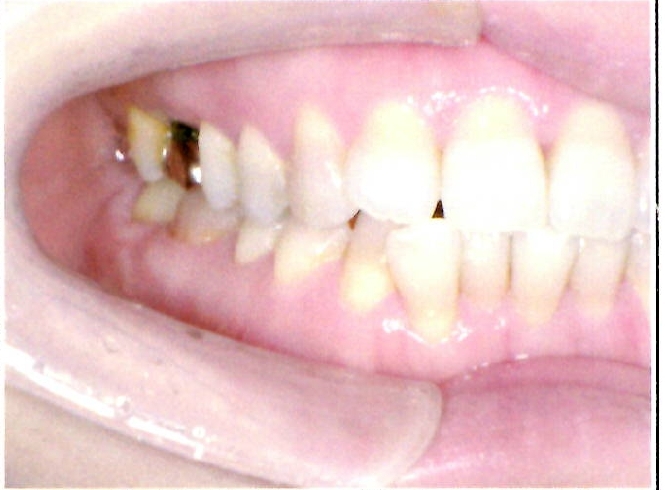

| 主訴・治療前の状態 | 前歯が噛み合っていない状態(開咬傾向)で、犬歯がやや前方に突出しており、見た目にお悩みがありました。 |

| 治療内容 | 上下左右の第一小臼歯(4番)計4本を抜歯し、そのスペースを利用して歯列を整え、前歯の噛み合わせを改善しました。 |

| 治療結果 | 前歯がしっかり噛み合うようになり、見た目も美しく整いました。患者様の満足度が非常に高かった症例です。 |